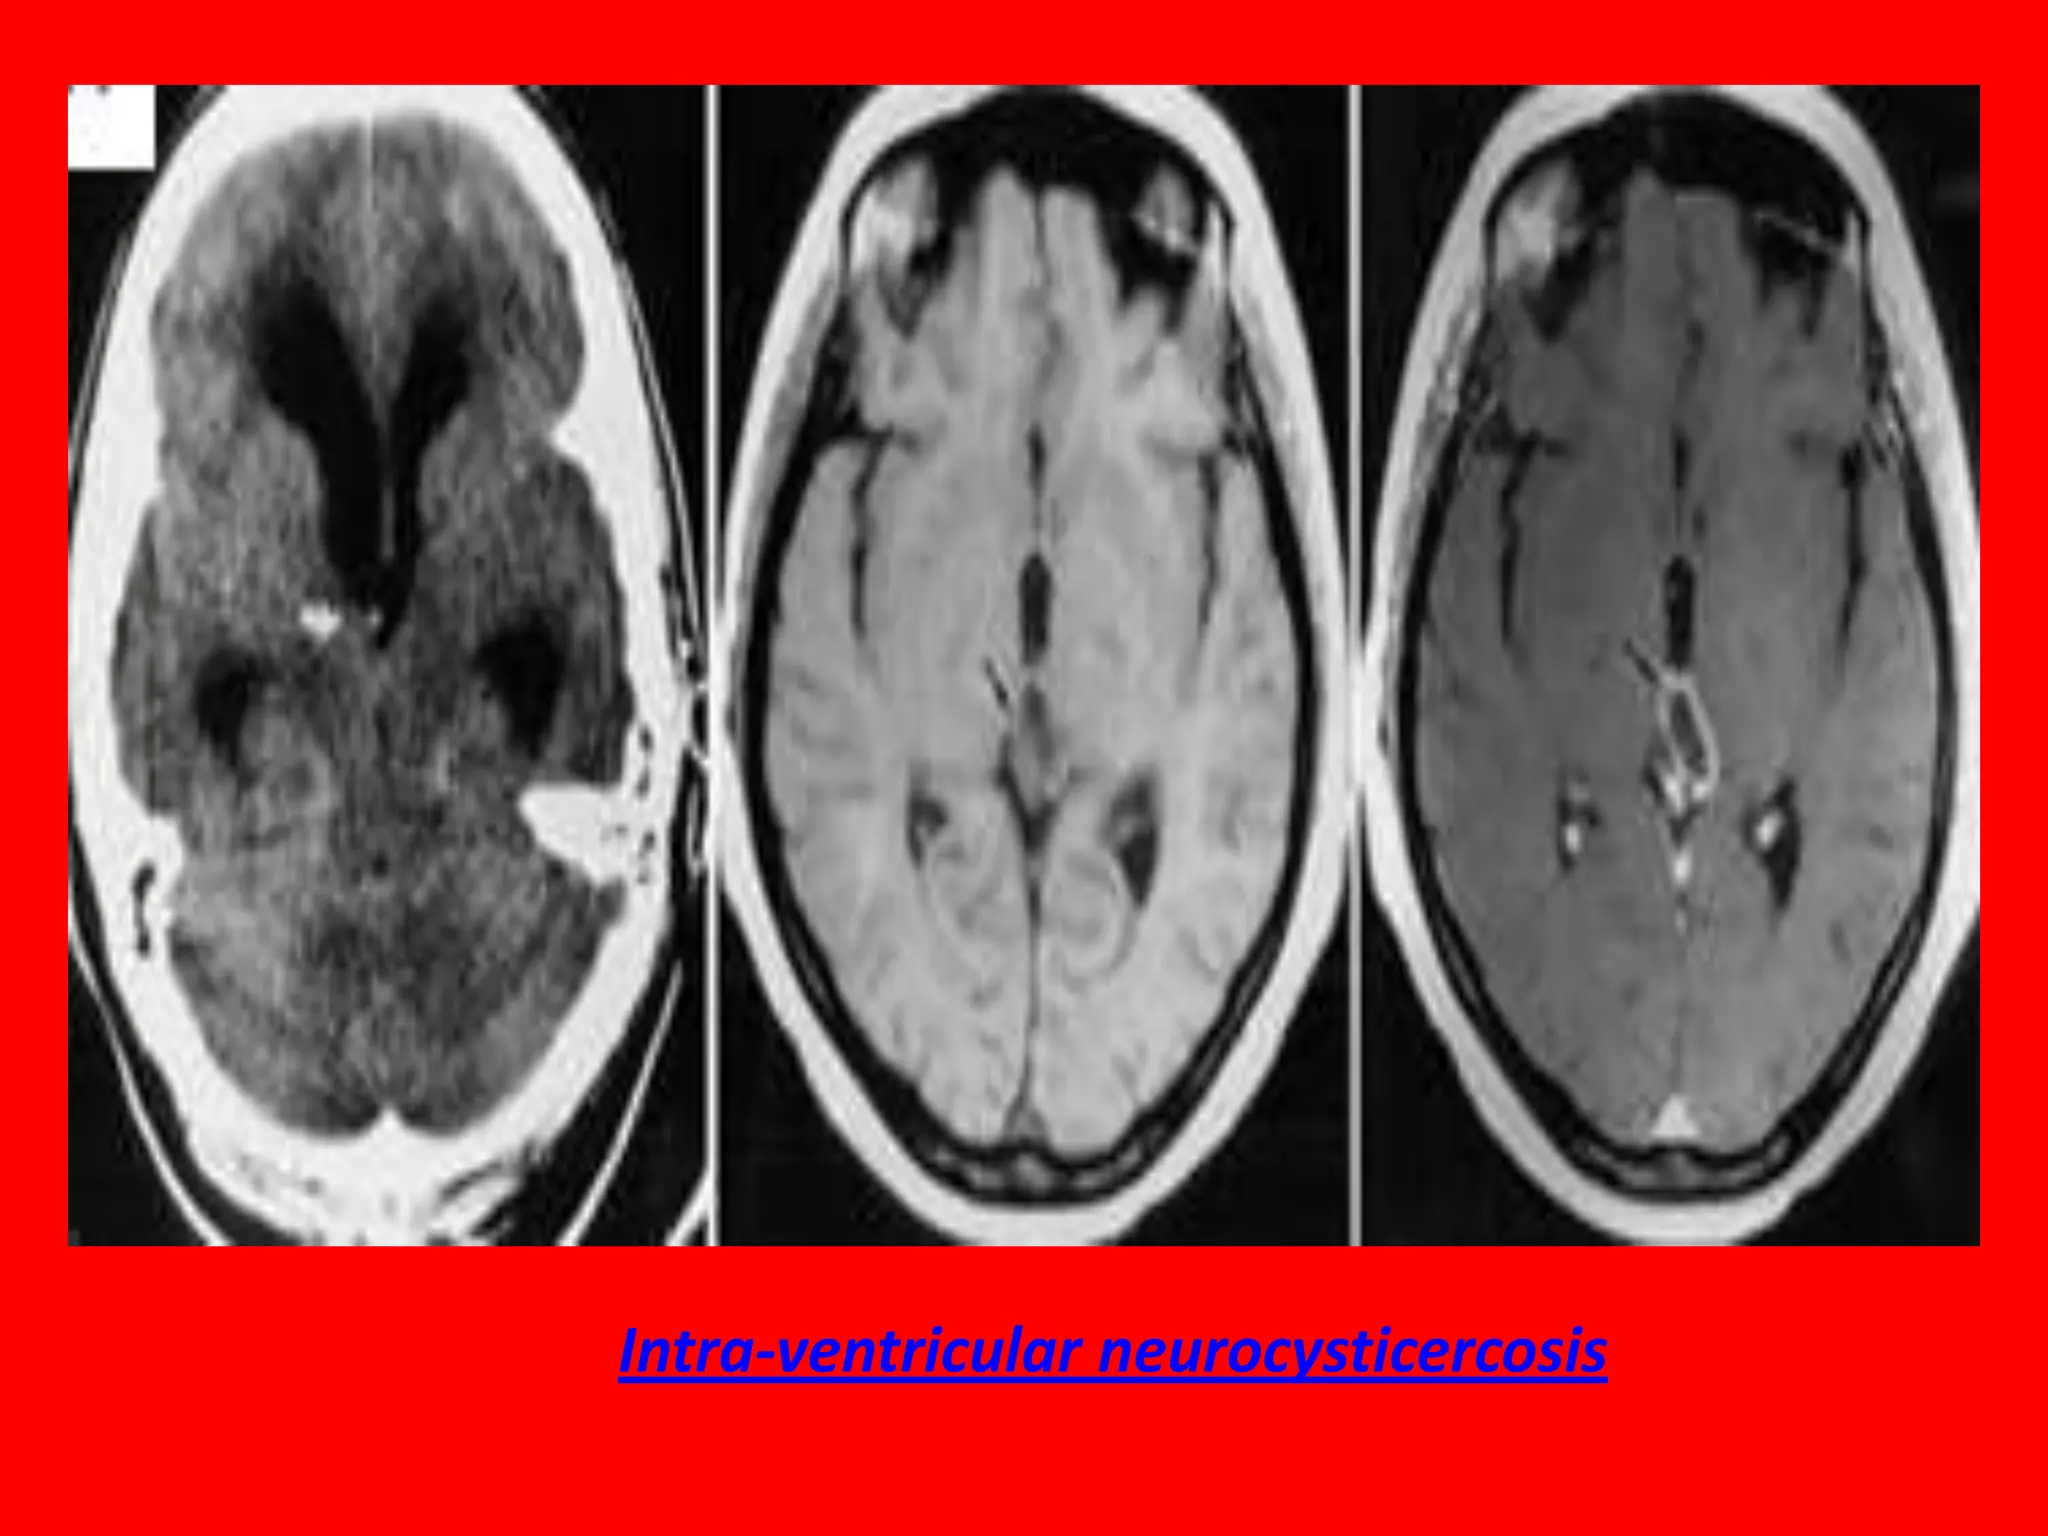

Cysticercosis is currently considered the most

common parasitic disease of the CNS. In about 10%

of neurocysticercosis cases, the cysts are found

within the cerebral ventricles or in cisterns. The

lesions are usually clinically silent until obstruction

occurs, secondary to either the location of the cystic

lesion or associated ependymitis caused by adjacent

granulomatous response. The most common

symptoms are related to hydrocephalus. The onset

of symptoms, including

headache, vomiting, seizures, can be rather sudden

and can result in death. A degenerating cyst can

cause symptoms of meningitis.

Intra-ventricular neurocysticercosis